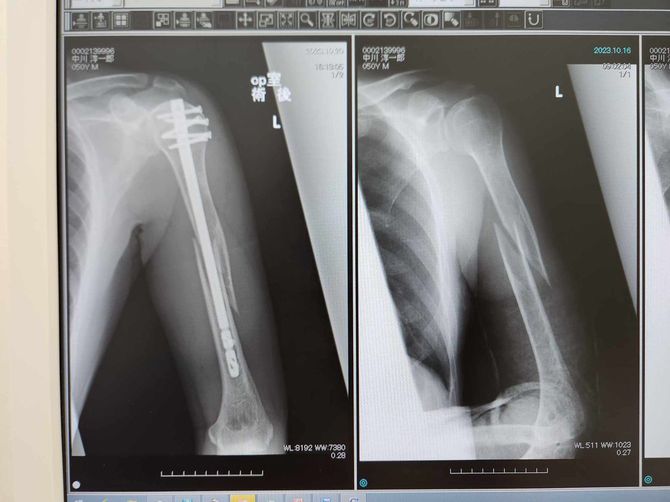

手術当日は執刀医が見事な施術で無事に処置を終えてくれた。骨を棒状のチタンとボルトで固定したので、あとは骨がくっつくのを待つのみである。術後の経過も順調で、ほどなくリハビリがスタート。担当してくれたPT(理学療法士)と私は妙に気が合い、腕を動かしてもらうリハビリの最中、ヘンな言い方だが毎日楽しかったのである。